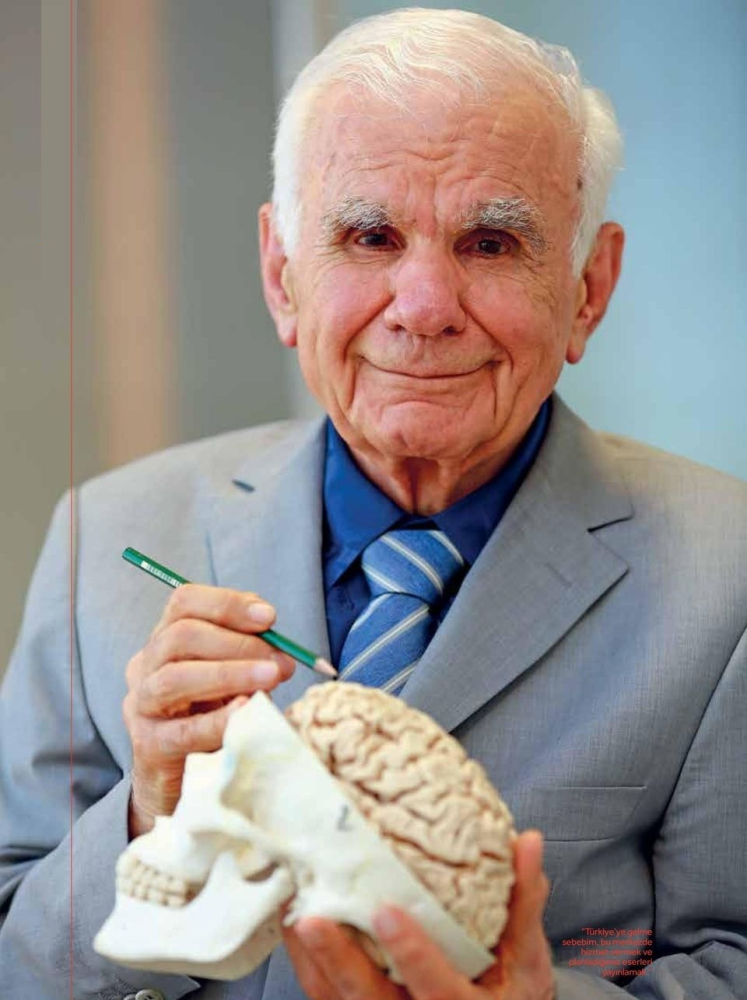

Amerikan Beyin Cerrahları Birliğince “Yüzyılın en iyi beyin cerrahı” seçilen Prof. Dr. Gazi Yaşargil, hekimlik kariyeri boyunca geliştirdiği cerrahi yöntemler ve yetiştirdiği uzmanlarla nöroşirurji alanının gelişmesine katkı sağladı.

Tıp eğitiminden sonra 3 ay Dr. Josef Klingler’in yanında beyin anatomisi üzerine çalışan Yaşargil, ardından nöroloji-psikiyatri, dahiliye ve genel cerrahi alanlarında asistanlık yaptı.

Mikronöroşirurji alanında öncü oldu

Bu süreçte Parkinson hastalığı ve hareket bozukluklarına yönelik stereotaktik cerrahi teknikler geliştiren Yaşargil, yüksek frekanslı koagülasyon yöntemini beyin cerrahisinde ilk kez kullanan isim oldu.

1960’lı yıllarda Parkinson hastalığına yönelik stereotaktik cerrahiler yapan Yaşargil, 1967’den itibaren mikrovasküler cerrahiyi insan beyninde uygulayarak modern mikronöroşirurjinin kurucusu olarak tarihe geçti.

Yaşargil, anevrizma, AVM, beyin tümörleri ve epilepsi cerrahisinde mikrotekniklerin yaygın kullanımını sağlayarak nöroşirurjide yeni bir dönem başlattı.